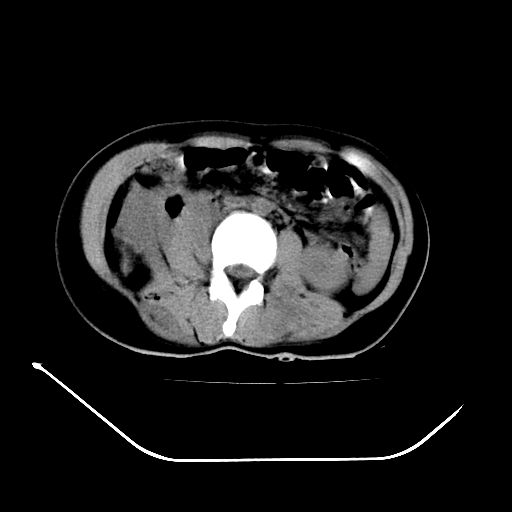

以下是引用liuyue在2008-7-19 13:02:00的发言:[br]1.肝右叶后下段及右肾挫裂伤伴腹腔积血。[br]2.右侧多发性肋骨骨折、横突骨折、右髂骨骨折伴周围软组织挫伤。[br]3.右侧腰大肌肿胀,并可见低密度影,如为气体,则肠道挫裂伤待除外。

以下是引用zhengfaming在2008-7-19 14:42:00的发言:[br]1.肝右叶后下段及右肾挫裂伤伴腹腔积血。脾脏挫裂伤待排[br]2.右侧多发性肋骨骨折、横突骨折、右髂骨骨折伴周围软组织挫伤。[br]3.右侧腰大肌肿胀,并可见低密度影,如为气体,则肠道挫裂伤待除外

以下是引用道哥在2008-7-19 16:52:00的发言:[br]肝右叶后下段及右肾挫裂伤、脾破裂伴腹腔积血。[br]2.双侧多发性肋骨骨折、横突骨折、右髂骨骨折伴周围软组织挫伤。[br]3.右侧腰大肌肿胀,并可见低密度影,如为气体,则肠道挫裂伤待除外。